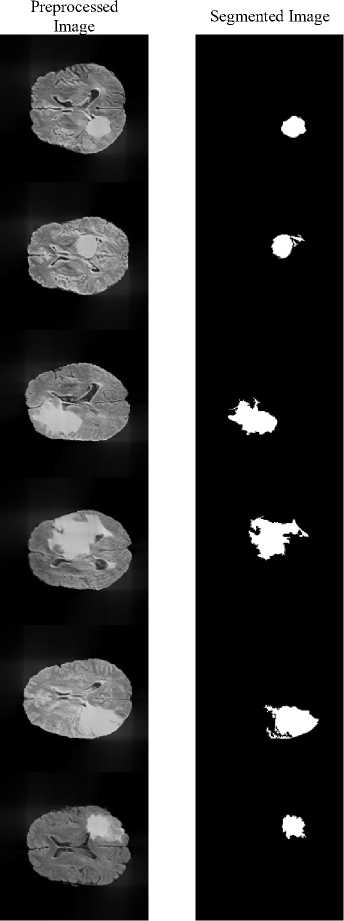

Input

Fig.5. Segmented Image using proposed system

The proposed method achieves a DSC of 0.9907 and a Jaccard Index of 0.9816, demonstrating excellent agreement with expert annotations and confirming that the framework precisely localizes and segments the tumor region rather than over-predicting background. Fig.5 illustrates the segmentation results, where the tumor regions are accurately delineated from the surrounding brain tissues.